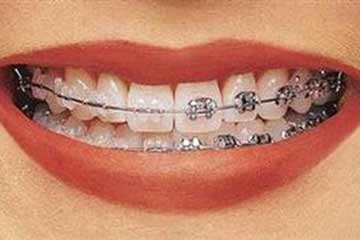

L'ortognatodonzia, disciplina che studia le disgnazie dento-maxillo-facciali, ha come finalità primaria quella dindividuare precocemente una noxa patogena, “creando le premesse per ricondurre nell'ambito della norma biologica la vis vitalis della crescita naturale”.

Il paziente ortognatodontico è, in genere, un soggetto in fase di crescita; tuttavia, sempre più frequentemente anche l'adulto richiede l'intervento dell'ortodontista, con esigenze soggettive e necessità cliniche oggettive sostanzialmente differenti, per le quali risulta spesso indispensabile un approccio interdisciplinare.

Riguardo ai tempi di trattamento non risulta sempre possibile stabilire con esattezza la durata della terapia ortodontica: nel soggetto in crescita, la pianificazione terapeutica può prevedere differenti fasi di intervento, con periodi intermedi, nel corso dei quali va monitorata la crescita e lo sviluppo del soggetto e la permuta dentale; nel soggetto adulto è spesso richiesto un approccio multidisciplinare.